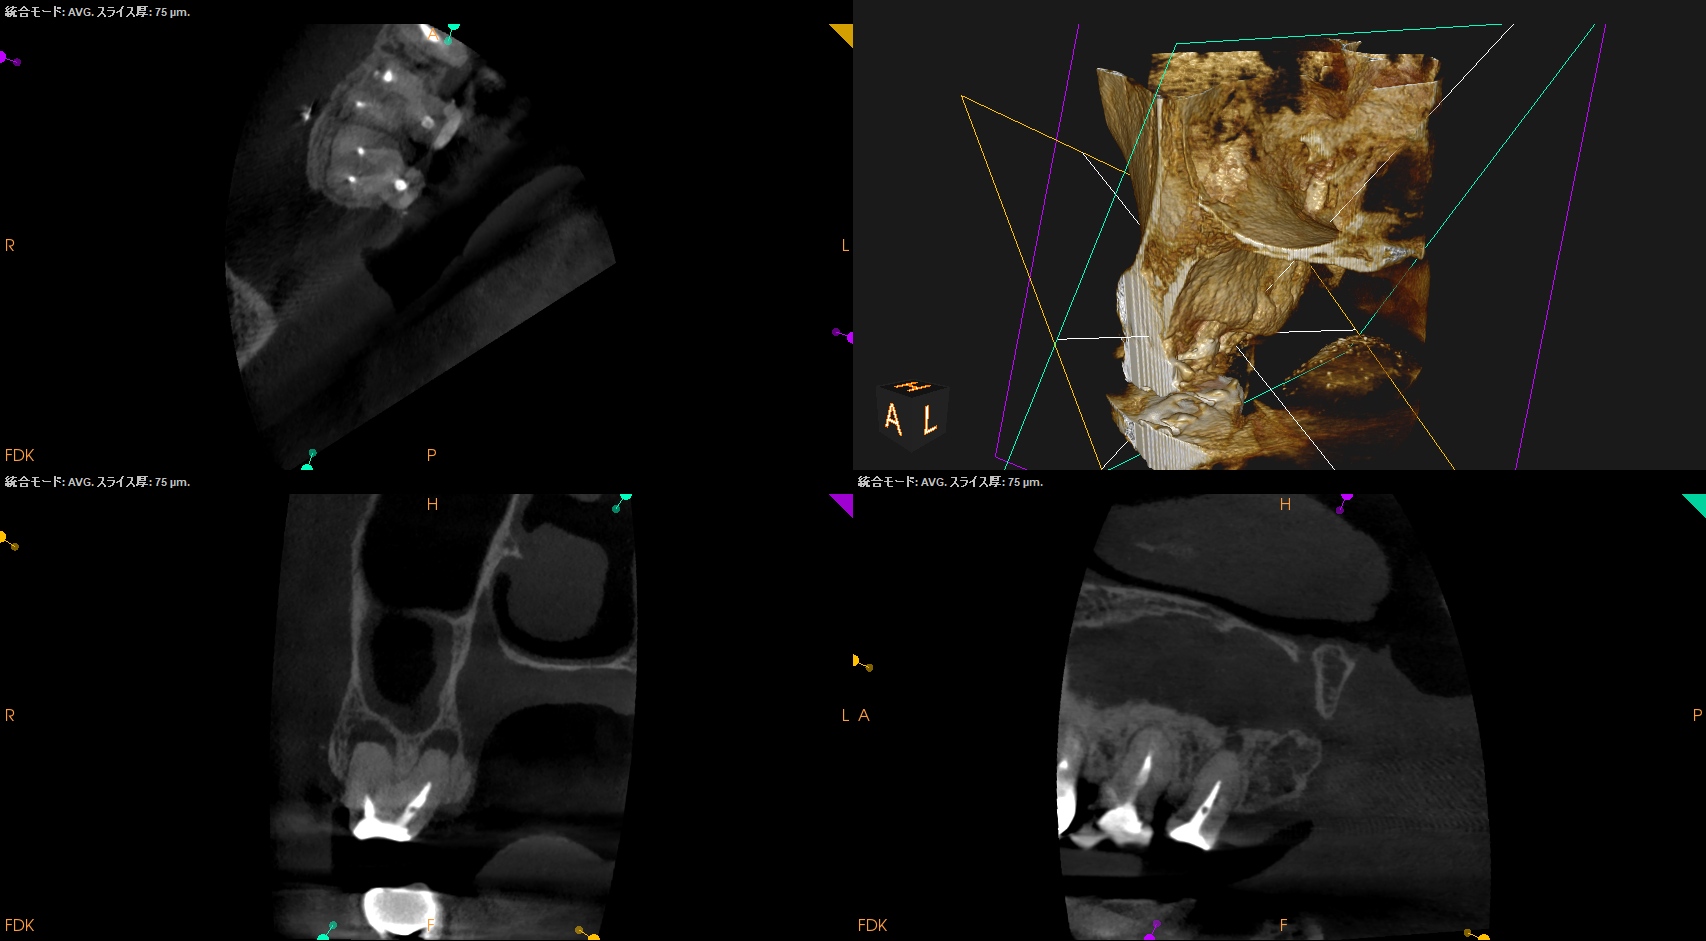

術後に口腔内PA, CBCTも撮影した。

MB

DB

P

ということで問題が客観的にないことがわかる。